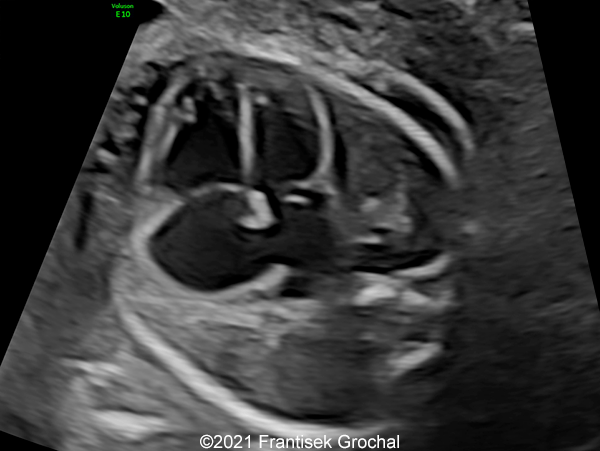

Case Report: A 24-year-old secundigravida, primipara presented to our office at 24 weeks and 6 days of her pregnancy due to a right-sided cranial parieto-occipital mass of the fetus. We obtained the following images.

Our ultrasound images at 24 weeks, 6 days show a highly vascularized, mostly solid mass measuring 58 x 45 x 34mm in the right-parieto-occipital subcutaneous region. Vascular supply of the lesion could be traced to the right vertebral artery. Repeat ultrasound exams done later in pregnancy demonstrated that the size of the mass remained stable with overall mass volume about 58 cm³.